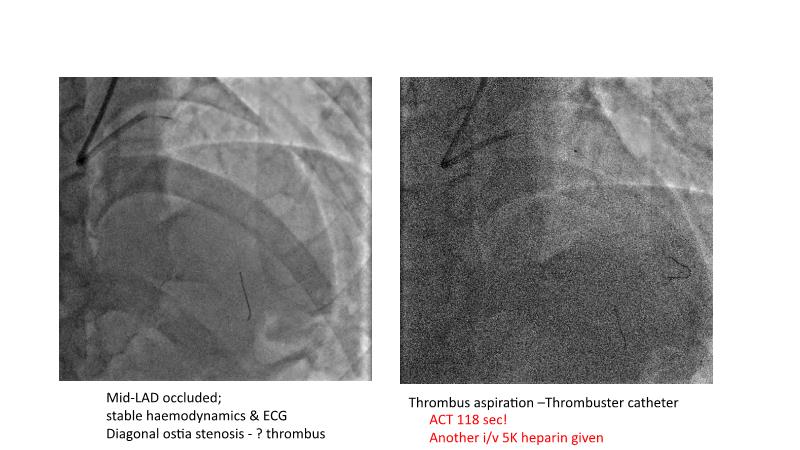

This session is recommended for you if you are seeking insights into the advantages of using IVUS imaging over visual assessment for better outcomes in left main bifurcation procedures. Discuss with experts the benefits of using RotaCUT in lesion preparation for left main bifurcation and explore the impact of high radial strength stents on the procedure's success.

• To understand why the use of IVUS imaging is different from seeing with experienced eyes to achieve improved left main bifurcation outcome